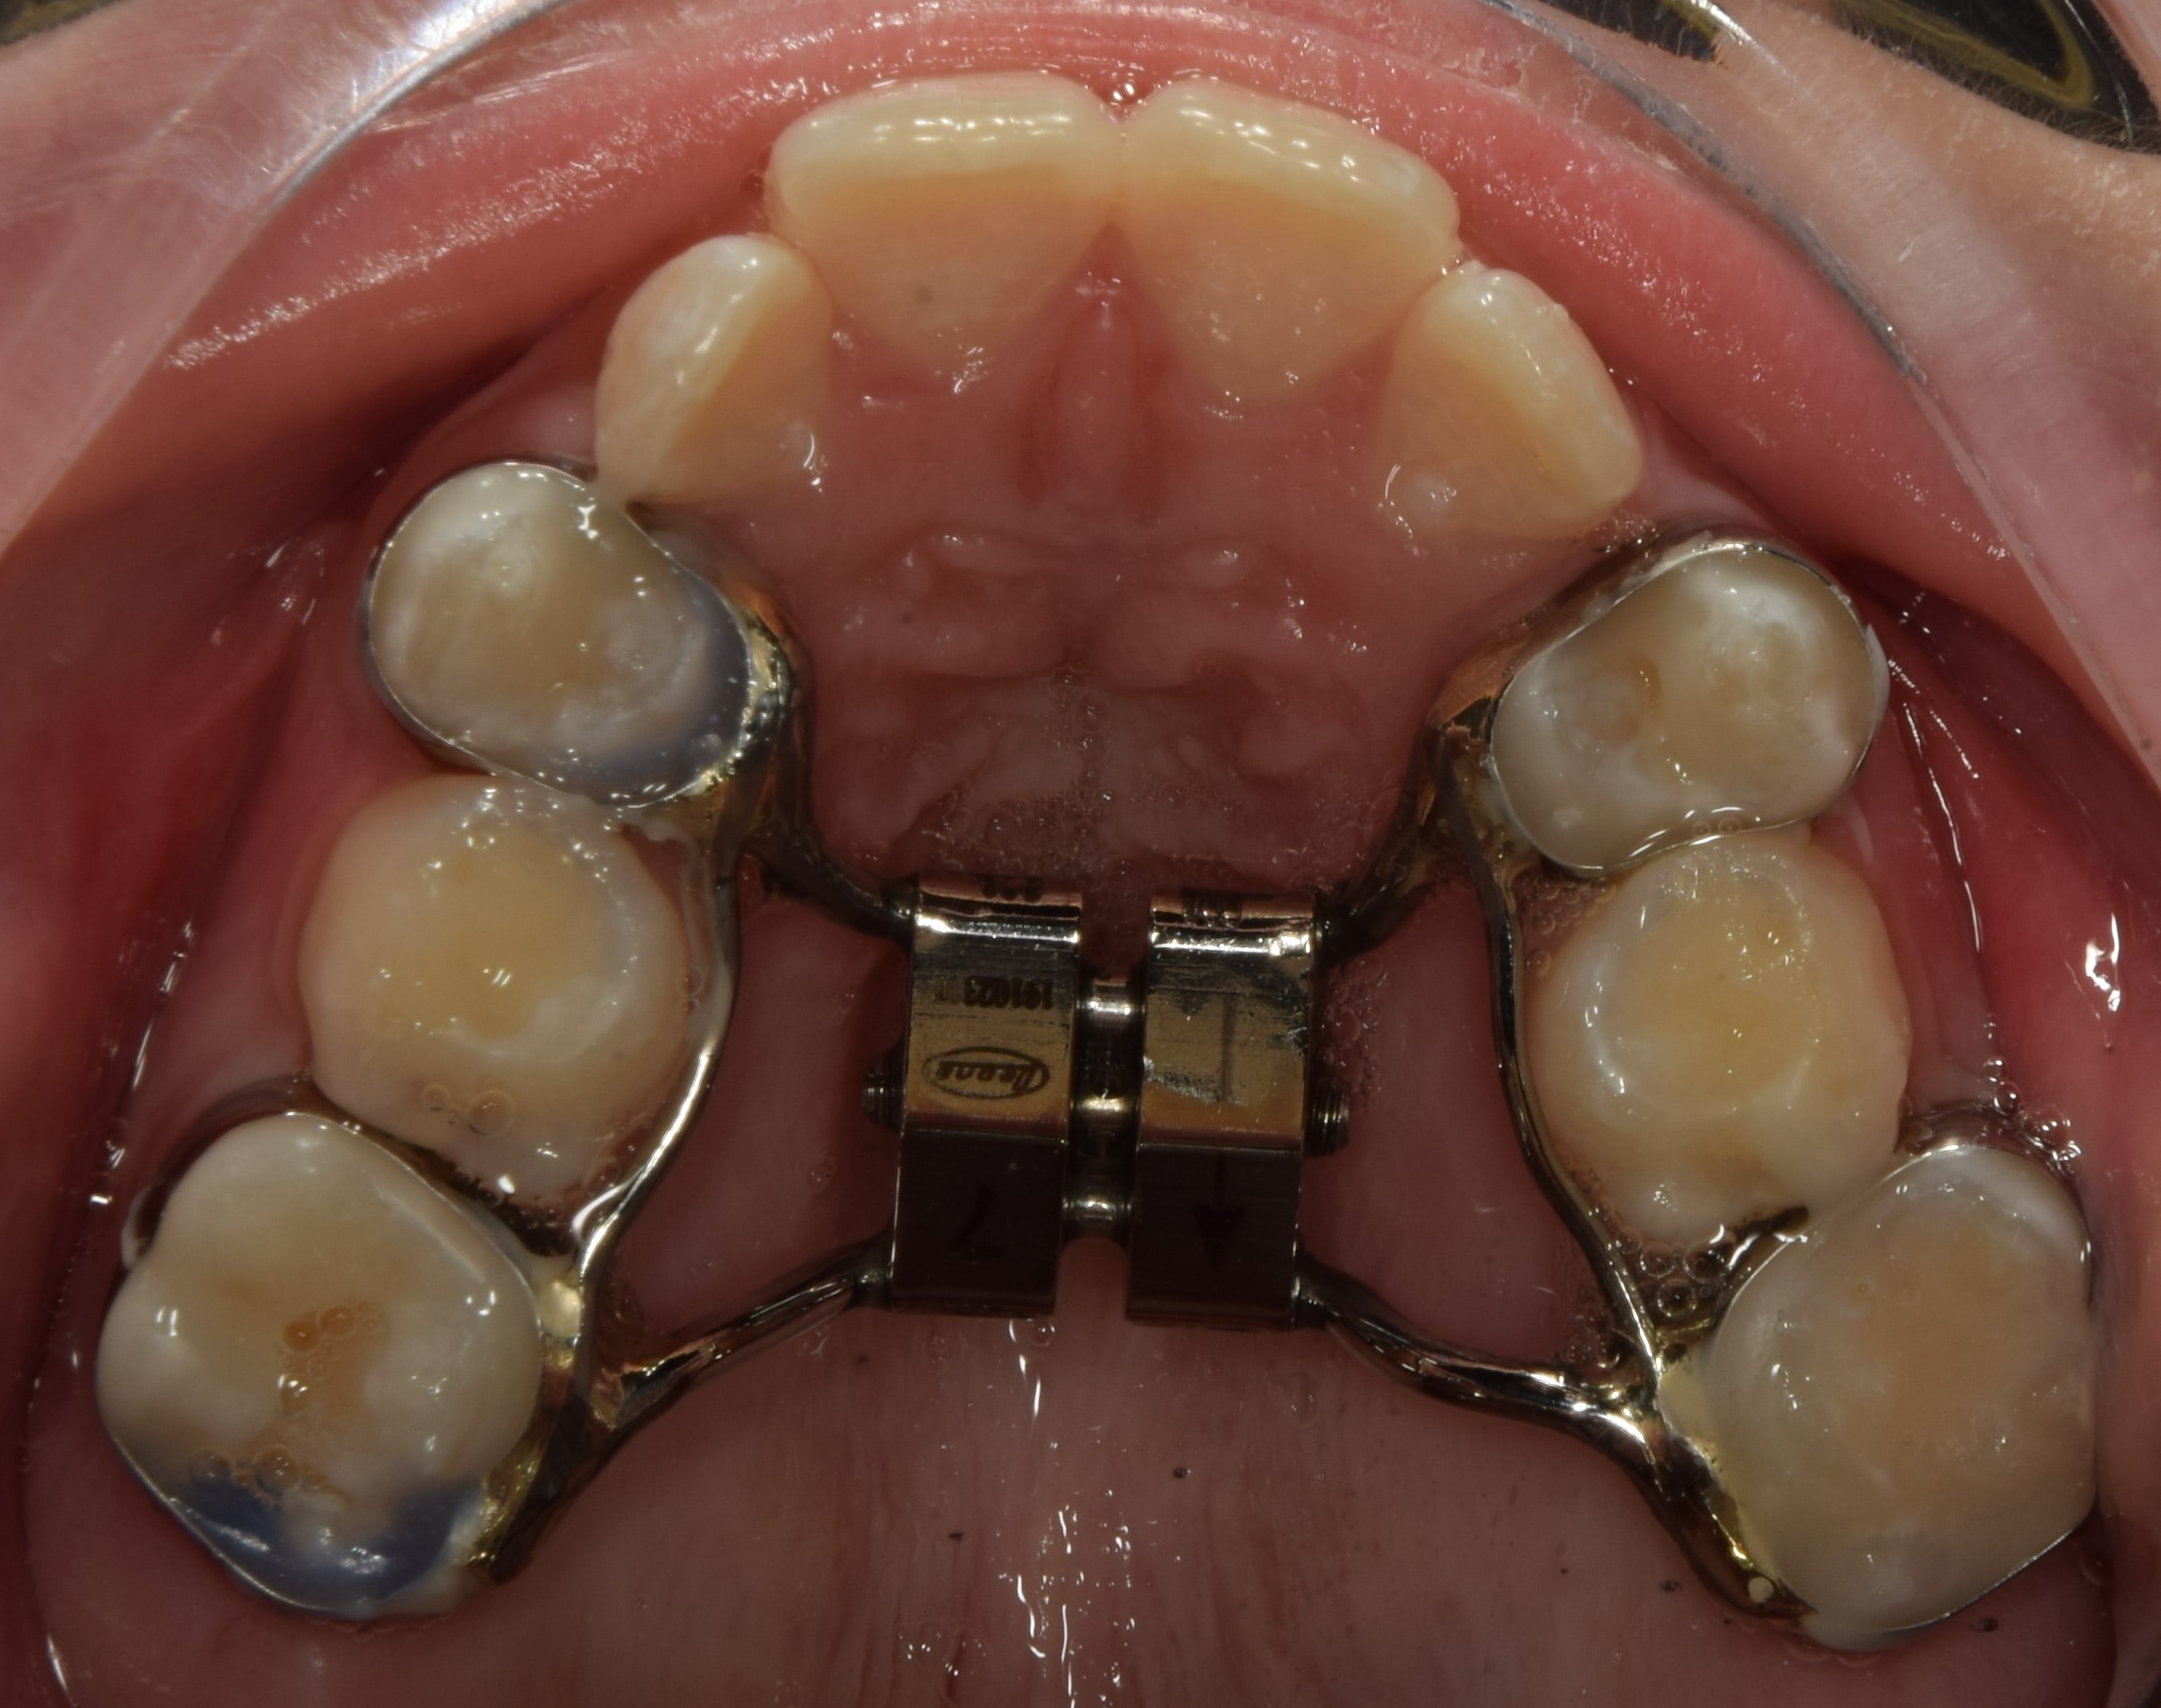

Hyrax

Fiatalkorban a felső állcsont tágítására alkalmas rögzített fogszabályozó készülék. Működése a felső állcsont közepén található csontvarrat (sutura palatina mediana) megnyitásán alapszik. Ilyenkor a két állcsontfelet távolítjuk egymástól. A hyrax maradófogazatban a felső első kisőrlőkön és első nagyőrlőkön rögzül, vegyesfogazatban pedig az első maradó nagyőrlőn és a tejőrlőkön (esetleg tej szemfogon). A vegyesfogazati hyrax készülhet fémből, vagy akrilátból (ez a splint hyrax). A hyrax közepén, a szájpad mélyére süllyesztve található egy csavar, amelyet a pácienseknek, szülőknek otthon kell tekerni. Fiatalkorban (7-9 év) ez 3 naponta 1 tekerést jelent, míg később (9-12 év) naponta 2 tekerést. A készülék működése során a felső állcsont tágul, a mosoly szélesedik, a torlódások spontán oldódnak, és a felső metszőfogak között rés keletkezik (ez idővel magától zárul). A felső állcsont tágulásával az alsó állcsont gyakran spontán előrehelyeződik (megoldva ezzel pl. egy disztálharapást). Átjárhatóbbá válnak a légutak, javul a szervezet és az agy oxigenizációja, ezzel a gyerkőcök alvása, kipihentsége, koncentrációja. Általam sokat használt és kedvelt készülék a hyrax. Fontos megjegyeznem, hogy a fent leírt, ijesztően hangzó mozgatások a pácienseim beszámolói alapján semmilyen fájdalommal nem járnak, és bár drasztikusnak tűnhet a folyamat, a gyerekek által egyik legjobban tolerált készülék. Kezelés hossza: 7-12 hónap. Kontrollok gyakorisága: az első 2-3 hétben hetente, később 4-8 hetente. A kezelés befejeztével vagy Goshgarian kerül fel az eredmény megtartására, vagy teljes rögzített fogszabályzó ragasztásával folytatódik a terápia.